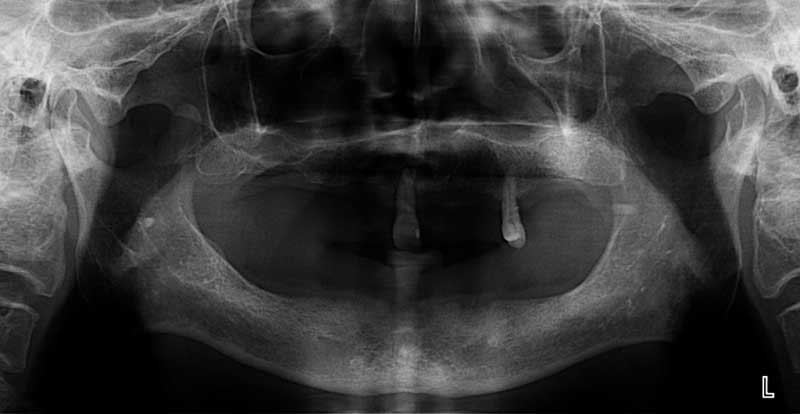

案例2